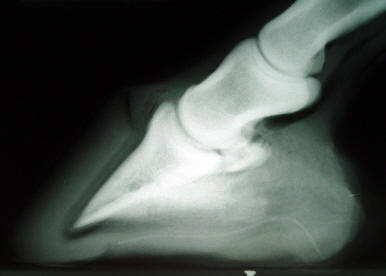

The corium

surrounding the tip of P3 in the above radiograph was exposed to

the outdoors. The attending veterinarian diagnosed chronic

laminitis, sole penetration and calcification of the lateral

cartilages. The deep rasp marks and the huge flattened area were

still visible in the sole in front of the frog! This work was

done in preparation for a "corrective" shoe. The collateral

groove depth at the apex was zero, and the groove depth at the

back of the foot was 1-3/4". The conditions here should be

immediately obvious to the educated naked eye, but I've seen

this too many hundreds of times to count. Why do so few notice?

The above right radiograph was taken six months later. I simply

allowed the horse to build adequate sole thickness under P3,

grew in a [more] attached toe wall, and kept the heels 1/16"

above the sole plane. This restored 100% soundness and usability

to the horse.